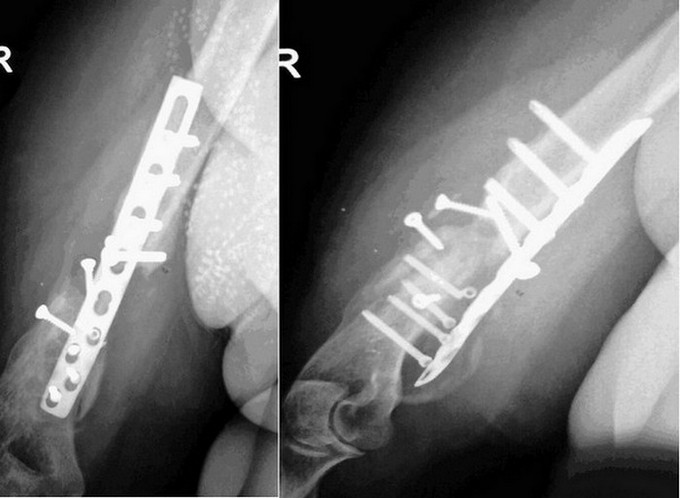

Пациентка 48 лет неоднократно оперирована по поводу перелома, а впоследствии ложного сустава плечевой кости. Последний раз около года назад, резекция ложного сустава с костной пластикой из гребня подвздошной кости. Результат вы видите на снимках. Из сопутствующей патологии только ЭКО III ст. Поступила к нам в отделение для дальнейшего лечения. По результатам анализов, и всех других обследований без отклонений. Местно: как обычно патологическая подвижность, умеренная болезненность, кожные покровы не изменены, не считая розового рубца. Конечно же вопрос - что делать? Варианты: штифт? Возможно... Костная пластика снова? Может АВФ с резекцией ложного сустава? Но почему-то хотелось бы этого варианта избежать, женщина все-таки. Кто-то из коллег предложил заполнить интрамедуллярный канал цементом и вставить штифт - большие сомнения в успехе мероприятия.PS кстати, в моей практике это не первая женщина с неоднократной попыткой похожего остеосинтеза и таким плачевным результатом. По поводу первичного остеосинтеза все понятно, без комментариев. А что делать, когда этот пациент уже твой больной?

Учитывая возраст, удалил бы металл, естественно ревизия зоны ложного сустава, думаю без костной пластики не обойтись.Синтез длинными пластинами для надмыщелков плеча, двумя: медиальной и латеральной. Гвоздь было бы хорошо,есть риск раскола дистального фрагмента из-за его "многострадальности"(остеопороз, склероз и т.д.). Тут дело опыта. Как то так. П/о период по ситуации.

В зависимости от местных традиций в большинстве фиксация перелома плеча проводится гвоздем или пластинами. Анализ осложнений показал, что небольшое преимущество имеют пластины! При фиксации гвоздем ложный сустав образуется зачет дистракции в зоне перелома, бывают и повреждения нерва во время блокировки и хронические боли из-за повреждения Rotator Cuff. А при открытой репозиции пластинами в основном осложняются мягкие ткани. Кроме этого, встречается осложнения из-за неправильного выбора размера пластины. Короткие пластины чаще осложнялись несращением, чем длинные. Установка винтов также имеет значение, доказано, что не количество винтов, а дистанция между винтами создает устойчивость!